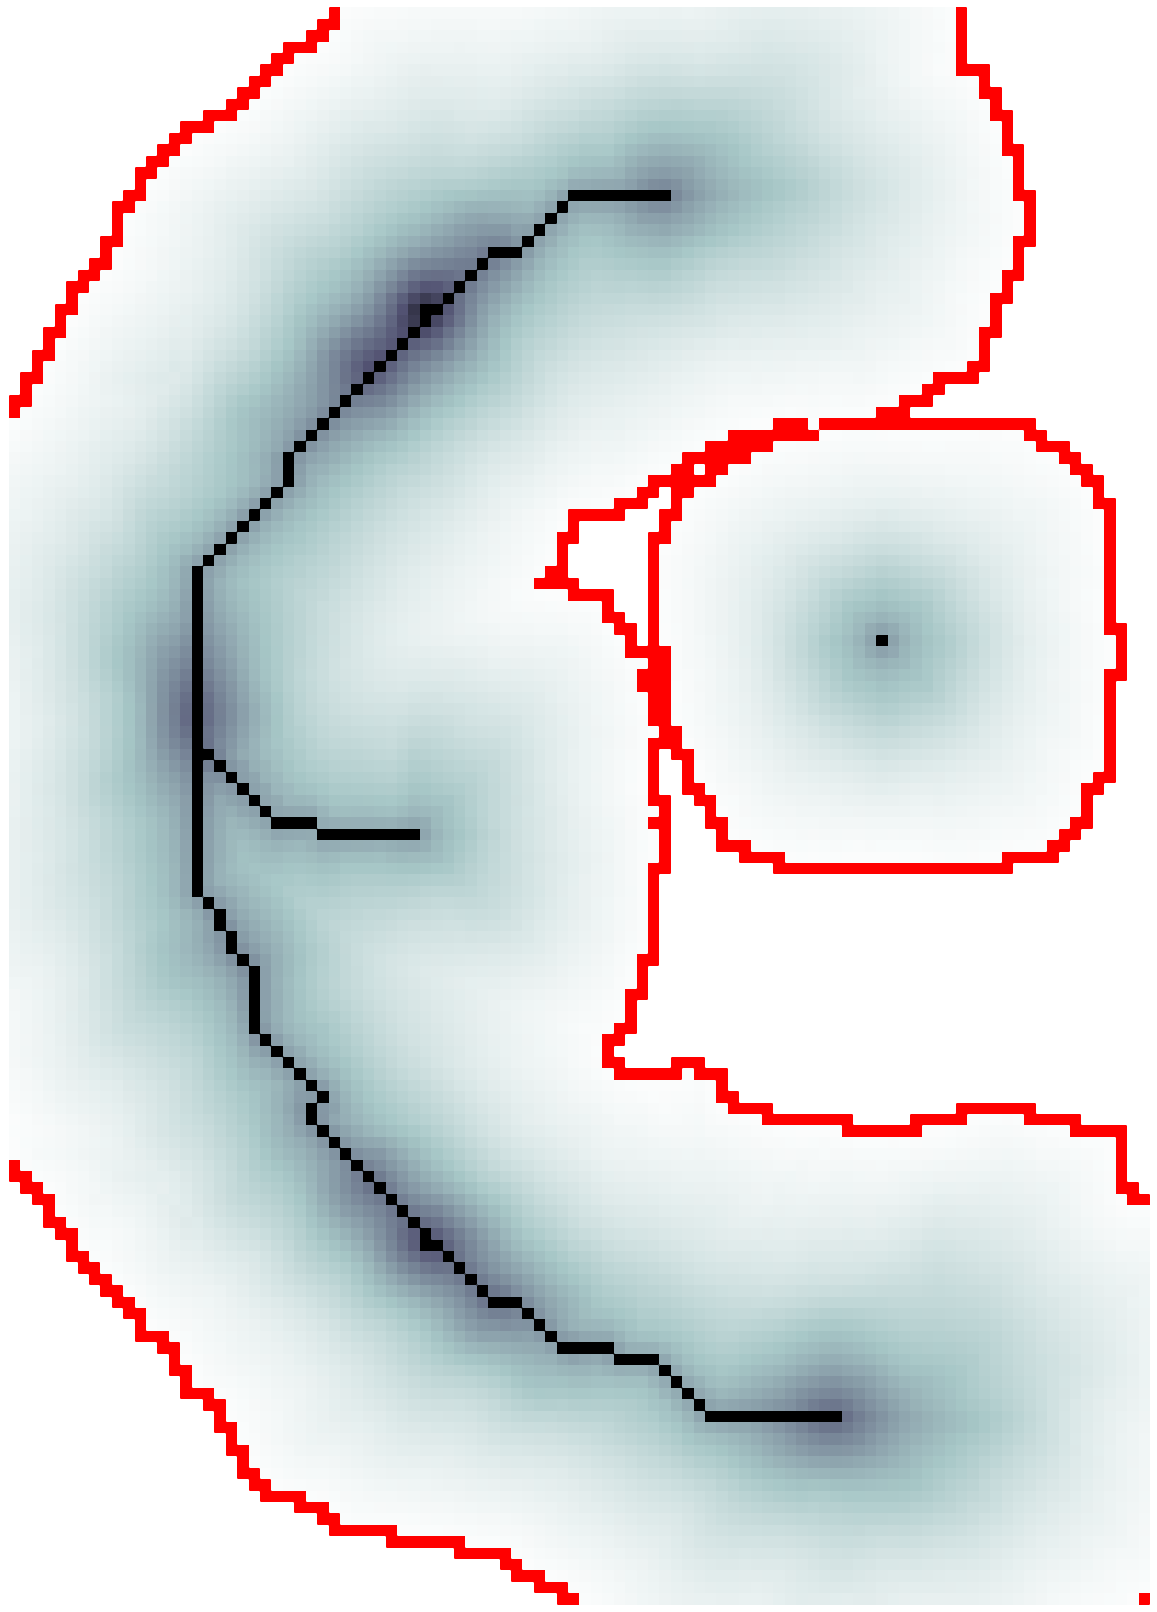

the respective semiaxes’ lengths. Conversely from , which is indeterminate, the tensor field is a symmetric positive definite (SPD) matrix for any . Here, the definition of the tensor kernel in (4) can be further reformulated exploiting the intrinsic log-concavity of . By mapping , a convex quadratic form is obtained, so that is an SPD, as the modelled tensor . In either case, the manifold of tensors can be mapped into a set of 6 independent components in the Log-Euclidean space, which greatly simplifies the computation of Riemannian metrics and statistics. We refer to [3] for a detailed methodological description. The continuous and smooth tensor field inherits the steerable property. Similarly to diffusion tensor MRI, the kernel shows a preferred diffusion direction for a given energy potential, e.g. the scalar function itself (fig. 1). This allows to define an arbitrary dictionary of filtering kernels (DFK) that embeds anisotropy and high-order directional features to scalar curvilinear templates, which enhances and locally resembles typical, smooth vessel patterns. Together with the arbitrary SLoGS DFK, we also introduce an extra pair of non-curvilinear kernels for completeness. These are the pseudo-impulsive , an isotropic derivative filter given by the Laplacian of Gaussian of , representing a Dirac delta function for . Also, the uniformly flat is another isotropic degenerate case, where the Laplacian of Gaussian derives from , which is assumed to be a uniform, constant-value kernel for . The purpose of introducing the extra kernels is to better contrast regions that most likely relate to vessel boundaries and to image background, respectively. Although and have singularities, ideally they represent isotropic degenerate kernels. Therefore we associate pure isotropic tensors for any given , so that (Identity). The respective directional kernel bases are undetermined.

where is the integral normalizing weight-map accounting for all vessel, boundary and background components; is the modulating SLoGS filter response at as in (7); is the steered Gaussian impulse response associated to the kernel ; is the Hann smoothing window in the neighbourhood centred at , and is one of the 6 components of the discrete steered tensors patch in the Log-Euclidean space. Note that all 6 tensorial components are equally processed, and that the neighbourhood and the SLoGS tensors patch have the same size. In (8), integrates also the isotropic contributions from vessel boundaries and background to better contrast the tubular structures’ anisotropy and to reduce synthetic artifacts surrounding the vessels (fig. 1). In particular, is averaged with an identically null tensor patch in the Log-Euclidean space in correspondence of boundaries and background, and is computed as in (7), where the image negative of is considered. Lastly, the connected vesselness maps and the associated synthetic tensor field are reconstructed by adding adjacent overlapping blocks in the OLA 3D grid for the given scale .

The scalar vesselness responses of both HCP and PC images are determined using the state-of-the-art Frangi filter (FFR) [8], and Optimally Oriented Flux (OOF) [12]. Also, the connected vesselness map (CVM) and the associated tensor field (TF) are synthesized for the same dataset using VTrails. The connectedness of the considered scalar maps is qualitatively assessed and the TF is inspected as proof of concept in section 3.1.

3.1 Connectedness of the Vesselness Map

Fig. 3 shows the connectedness of vessels recovered from state-of-the-art vascular enhancers and curvilinear ridge detectors FFR and OOF together with the proposed CVM for the synthetic HCP and the real PC images.

On the synthetic phantom, FFR shows a fragmented and rough vesselness response in correspondence of irregularly shaped sections of the structure. Also, the response at the bifurcation is not smoothly connected with the branches (triangular loop). Conversely, OOF recovers the phantom connectedness at the branch-point, and the vesselness response is consistent along the tortuous curvilinear section, however ghosting artifacts are observed as the shape of the phantom becomes irregular (C-like) or differs from a cylindrical tube. Also, close convoluted structures, which change scale rapidly in the HCP, produce inconsistent responses of OOF (fig. 3). CVM shows here a strongly connected vesselness response in correspondence of both regular and irregular tubular sections, with local maxima at structures’ mid-line. The connectedness of the structures is emphasized regardless the complexity of the shape, and it resolves spatially the tortuous curvilinear ‘kissing vessels’ without additional ghosting artifacts, despite the smooth profile.

Similar results are observed on the PC dataset: FFR has a poor connected response in the noisy and low-resolution image. Vessels are overall enhanced, however thin and fragmented structures remain disconnected. Overall, the vesselness response is not uniform within the noisy structures, where maximal values are often off-centred. A more consistent response is obtained from OOF, where the connectedness of vessels is improved. Maximal response is observed at the mid-line of vessels, however, noise rejection is poor. CVM strongly enhances here the vessel connectivity. The fragmented vessels of PC have a continuous and smooth response in CVM with higher values and a more defined profile. Large vessels shows solid connected regions with local maxima at mid-line as in OOF. Conversely from OOF, CVM shows improved noise rejection in the background.

The respective tensor fields (TF) synthesized on both HCP and PC show consistent features. The TF’s characteristics are in line with the connectedness of CVM: enhanced and connected vessels are associated with high anisotropy, whereas background areas show a predominant isotropic component.